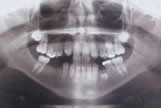

Panoramic X-Ray is a Picture of teeth, bones and soft tissues around them to help find problems which are not diagnosed with examination.

Panoramic X-Ray is a method which helps the dentist to diagnose the problems in teeth or gum. For example, X-Ray pictures can show cavities, hidden dental structures (such as wisdom teeth), and bone loss that cannot be seen during a visual examination. Also, these X-Rays do Show problems such as impacted teeth, bone anormalities, cysts, tumors, infections and fractures.